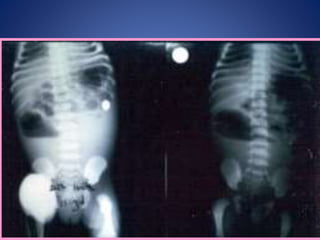

IMÁGENES CLASICAS DIAGNOSTICAS EN

EL 20%

Pruebas diagnosticas • Ecografía •Tomografía axial computarizada • Resonancia magnética nuclear • Lavado peritoneal diagnóstico • Laparoscopia • Radiografía de tórax • Placas simples de abdomen

IMÁGENES CLASICAS DIAGNOSTICASEN EL 20% SENSIBILIDAD 10%